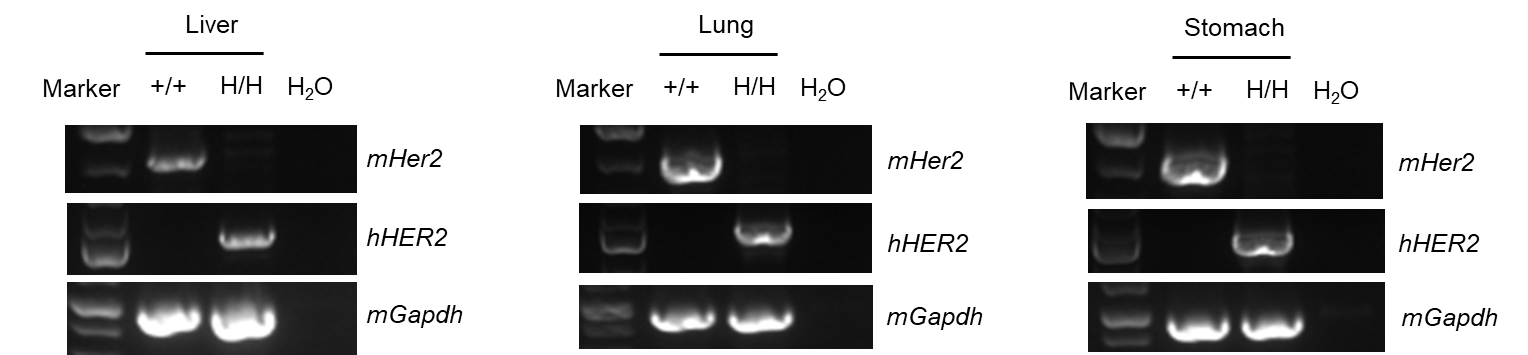

- Mouse Her2 mRNA was detectable only in wild-type B-NDG mice. Human HER2 mRNA was detectable only in homozygous B-NDG hHER2 mice but not in wild-type mice.

- Human HER2 was detected in the lung, liver, stomach, colon, small intestine, uterus, breast and kidney of homozygous B-NDG hHER2 mice.

mRNA expression analysis

Strain specific analysis of HER2 mRNA expression in wild-type B-NDG mice and B-NDG hHER2 mice by RT-PCR. Liver, lung and stomach RNA were isolated from wild-type B-NDG mice (+/+) and homozygous B-NDG hHER2 mice (H/H), then cDNA libraries were synthesized by reverse transcription, followed by PCR with mouse or human HER2 primers. Mouse HER2 mRNA was detectable only in wild-type B-NDG mice. Human HER2 mRNA was detectable only in homozygous B-NDG hHER2 mice but not in wild-type mice.